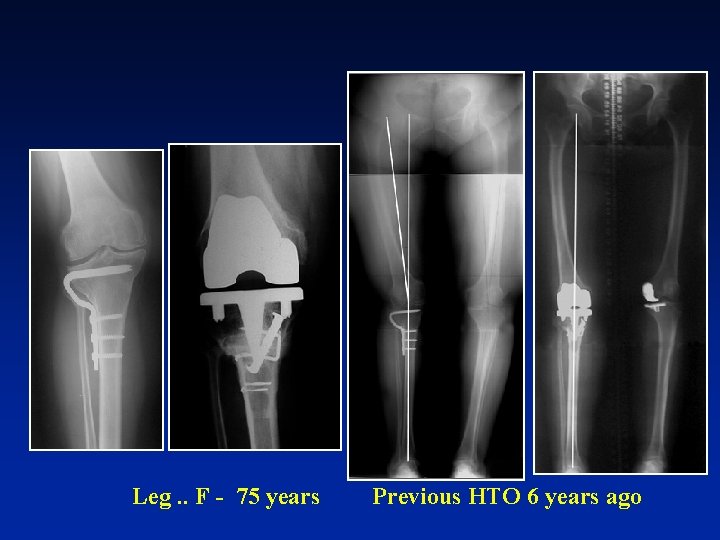

Leg. . F - 75 years Previous HTO 6 years ago

unipodal

Standing position Ant drawer Post drawer INNEX mobile bearing knee